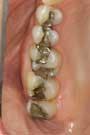

The “before” images work best to display patients’ current smiles and their shortcomings. Even though this may sound discordant, a clinical shot with harsher lighting to the face helps patients truly see the problems with their teeth and smiles (fig. 5). Request the patient wear little or preferably no makeup for the “before” pictures. Additionally, the umbrella-type lights can be manipulated to illustrate that those large alloy restorations darkening their bicuspid areas do indeed detract from their smiles (fig. 6). Side shots at approximately two feet also help illustrate maligned anterior teeth (figs. 7 and 8). I’ll often tell the patient, “This is the view that people sitting next to you, not across from you, see when they look at you.”